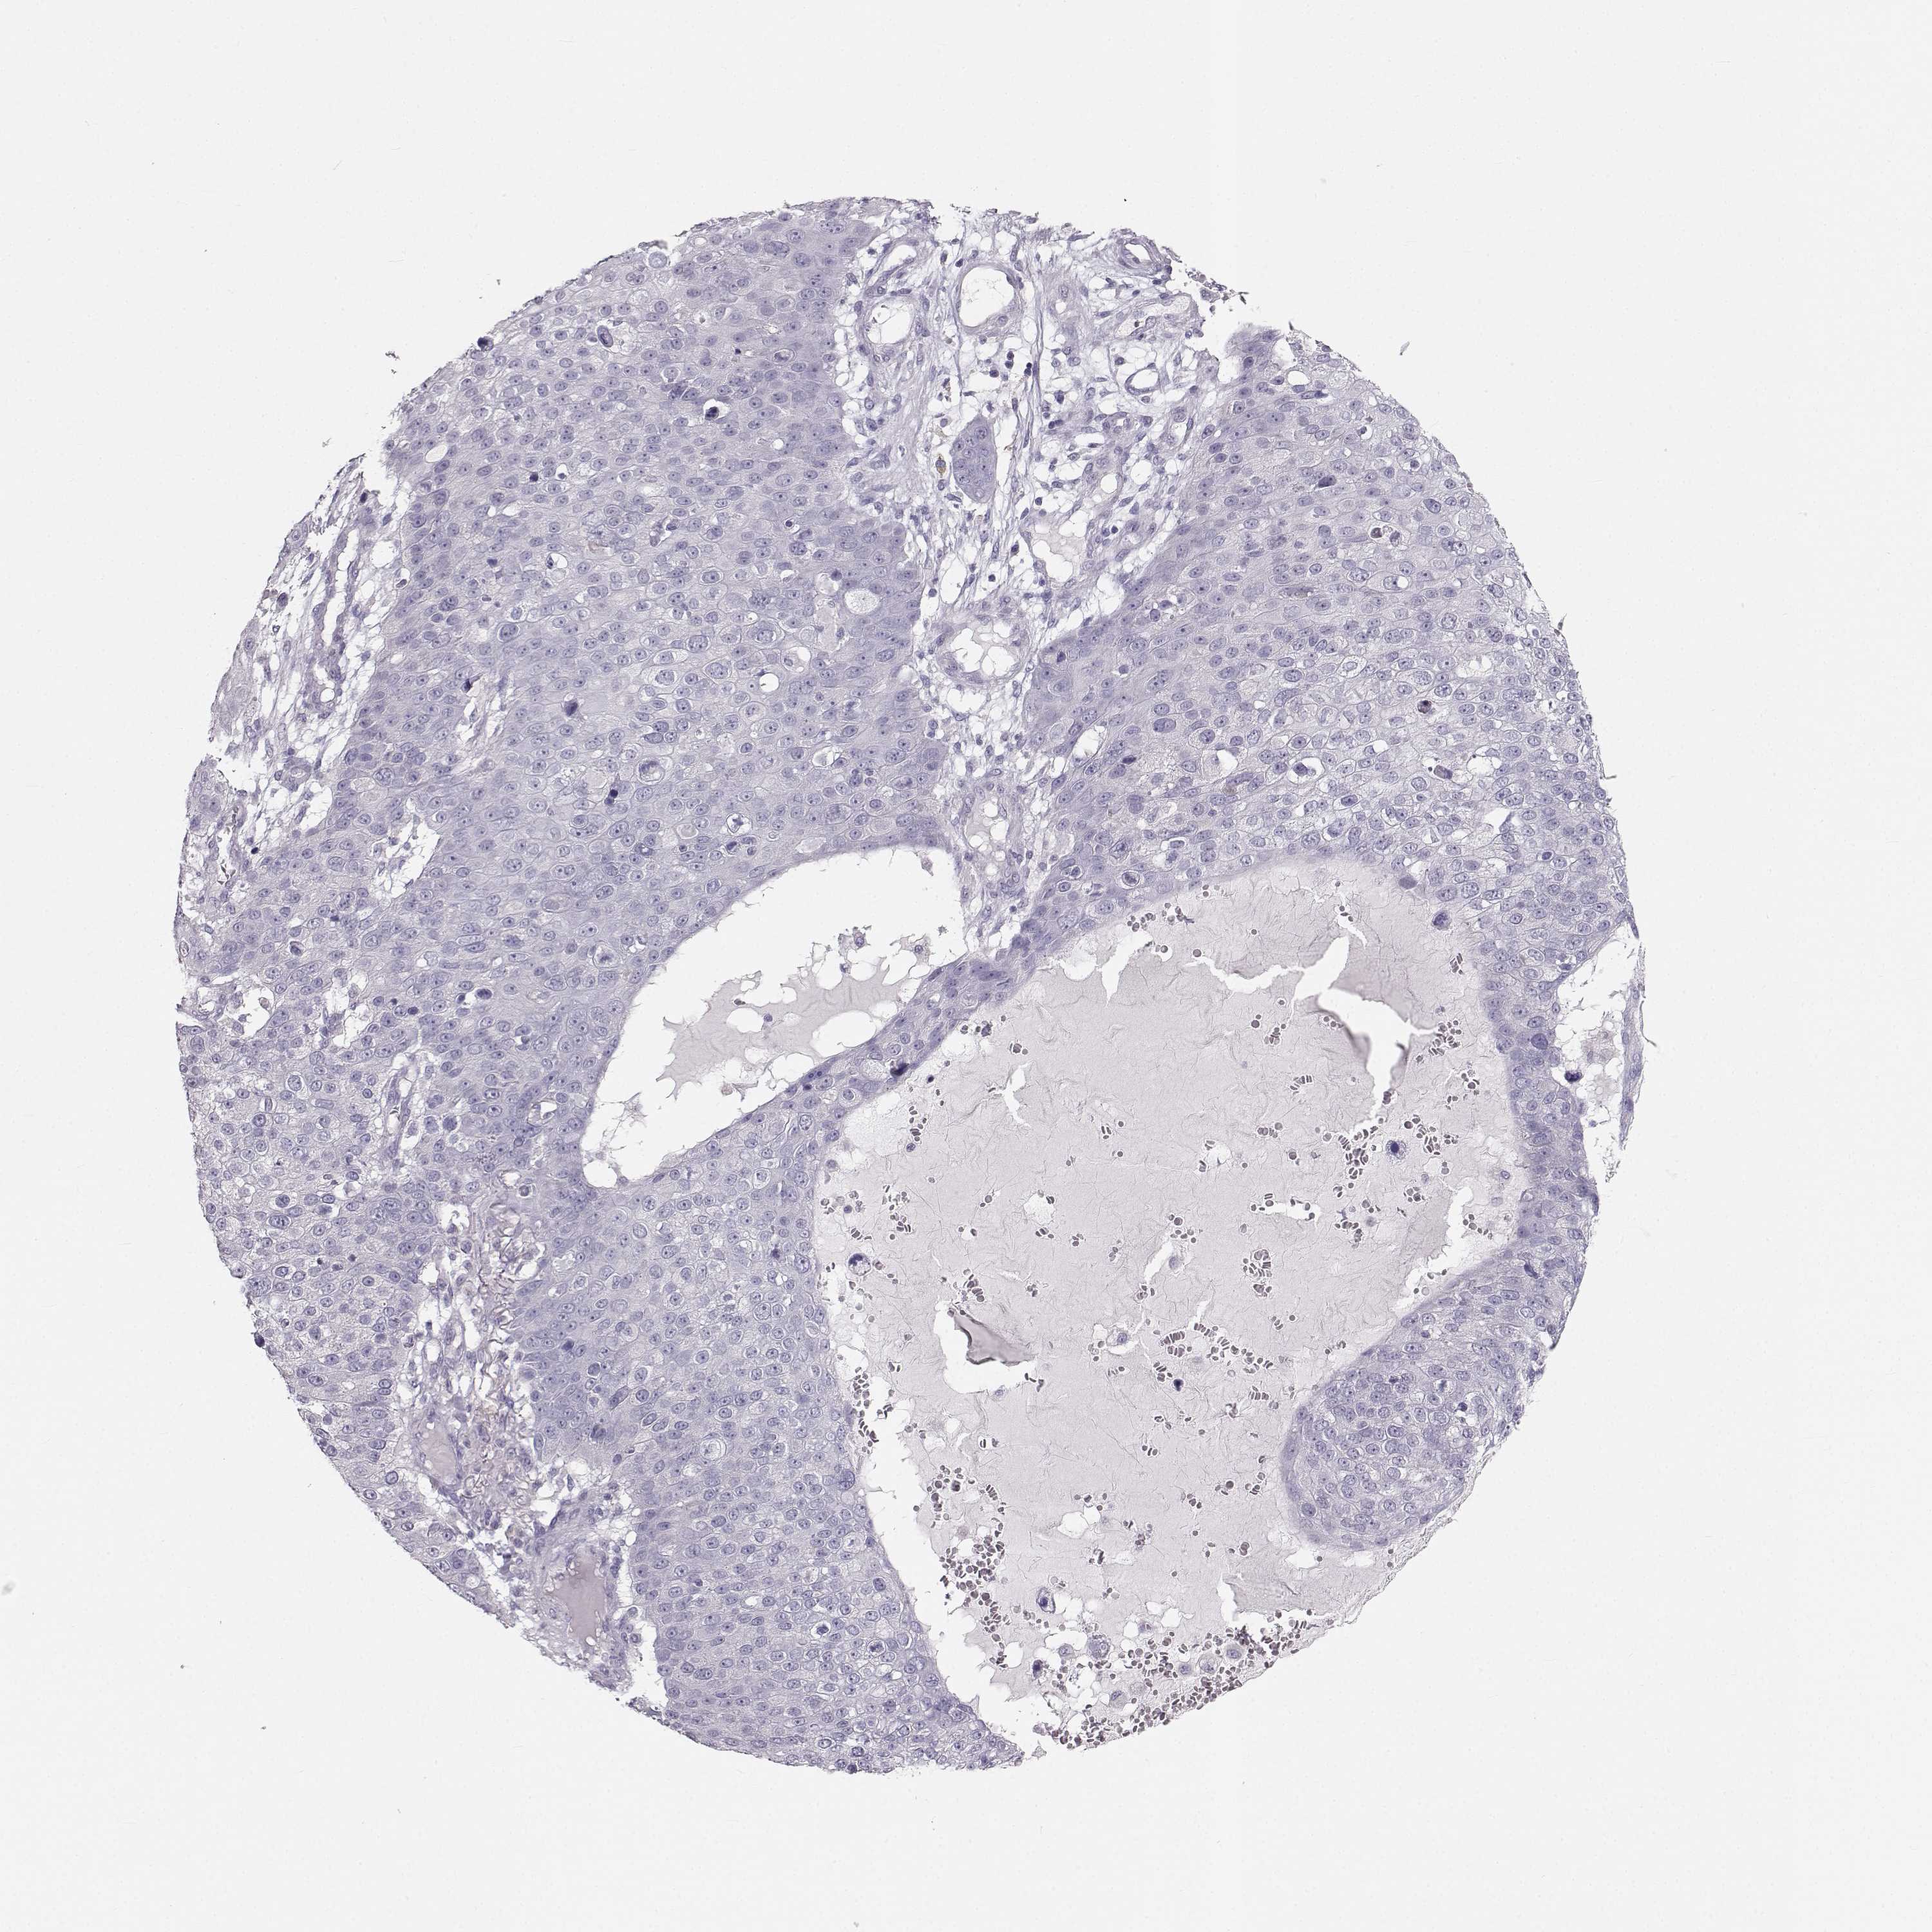

Basal cell and squamous cell cancer

SKIN CANCER - Protein expressioni

A mouse-over function shows sample information and annotation data. Click on an image to view it in a full screen mode. Samples can be filtered based on level of antibody staining by selecting one or several of the following categories: high, medium, low and not detected. The assay and annotation is described here.

Antibody stainingi

Antibody staining in the annotated cell types in the current human tissue is reported as not detected, low, medium, or high, based on conventional immunohistochemistry profiling in selected tissues. This score is based on the combination of the staining intensity and fraction of stained cells.

Each image is clickable and will lead to virtual microscopy that enables deeper exploration of all samples and also displays staining intensity scores, fraction scores and subcellular localization as well as patient and tissue information for each sample.

Antibody HPA052271

Antibody HPA059602

Staining

High

Medium

Low

Not detected

Intensity

Strong

Moderate

Weak

Negative

Quantity

>75%

75%-25%

<25%

None

Location

Nuclear

Cytoplasmic/membranous

Cytoplasmic/membranous,nuclear

Basal cell carcinoma

Squamous cell carcinoma, NOS